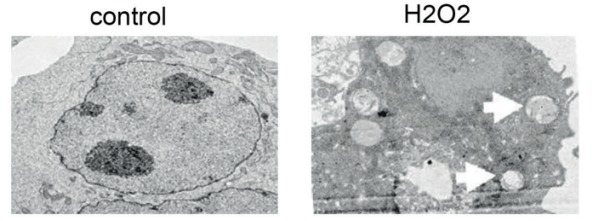

1)透射电镜观察自噬体。

自噬体是自噬的标志性结构。自噬体属于亚细胞结构,直径一般为300~900nm,平均500nm,普通光镜下看不到。通过透射电子显微镜发现自噬体一直是观察自噬现象最直接、最经典的方法,是自噬检测的“金标准”。

图片来源:Eur Rev Med Pharmacol Sci. 2017 Dec;21(24):5548-5556